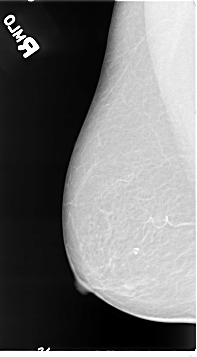

B_3066_1.RIGHT_MLO

RIGHT_CC LINES 4584 PIXELS_PER_LINE 2600 BITS_PER_PIXEL 12 RESOLUTION 50 NON_OVERLAY

RIGHT_MLO LINES 4632 PIXELS_PER_LINE 2560 BITS_PER_PIXEL 12 RESOLUTION 50 NON_OVERLAY